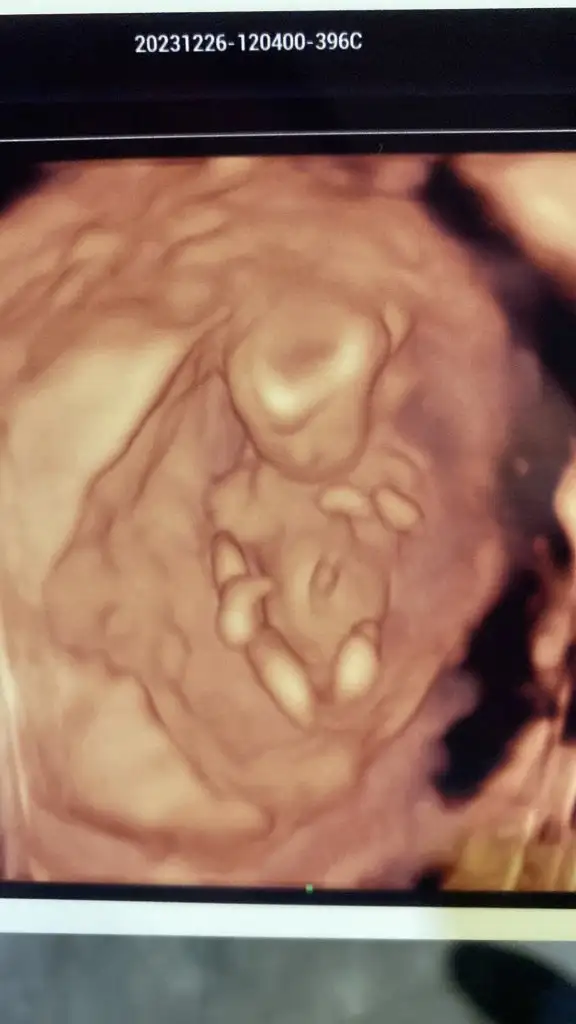

banada bakar mısınız kızlar bebişim sizce kız mı erkek mi?Merhaba ilk doktorum %70 kız dedi değişebilir dedi şuan 14. Haftayım görüntü de bişey söylemedi değişti mi yoksa kız mı? Anlamıyorum![]()

Bizede yorum yapabilir mısınız acaba☺Cnm senin erkek gibi duruyor tam göstermemiş ama![]()

Merhaba benimkine de bakar mısınız vajinal ultrasonBen nuruna gore anlıyorum kızınız olucak inşallah